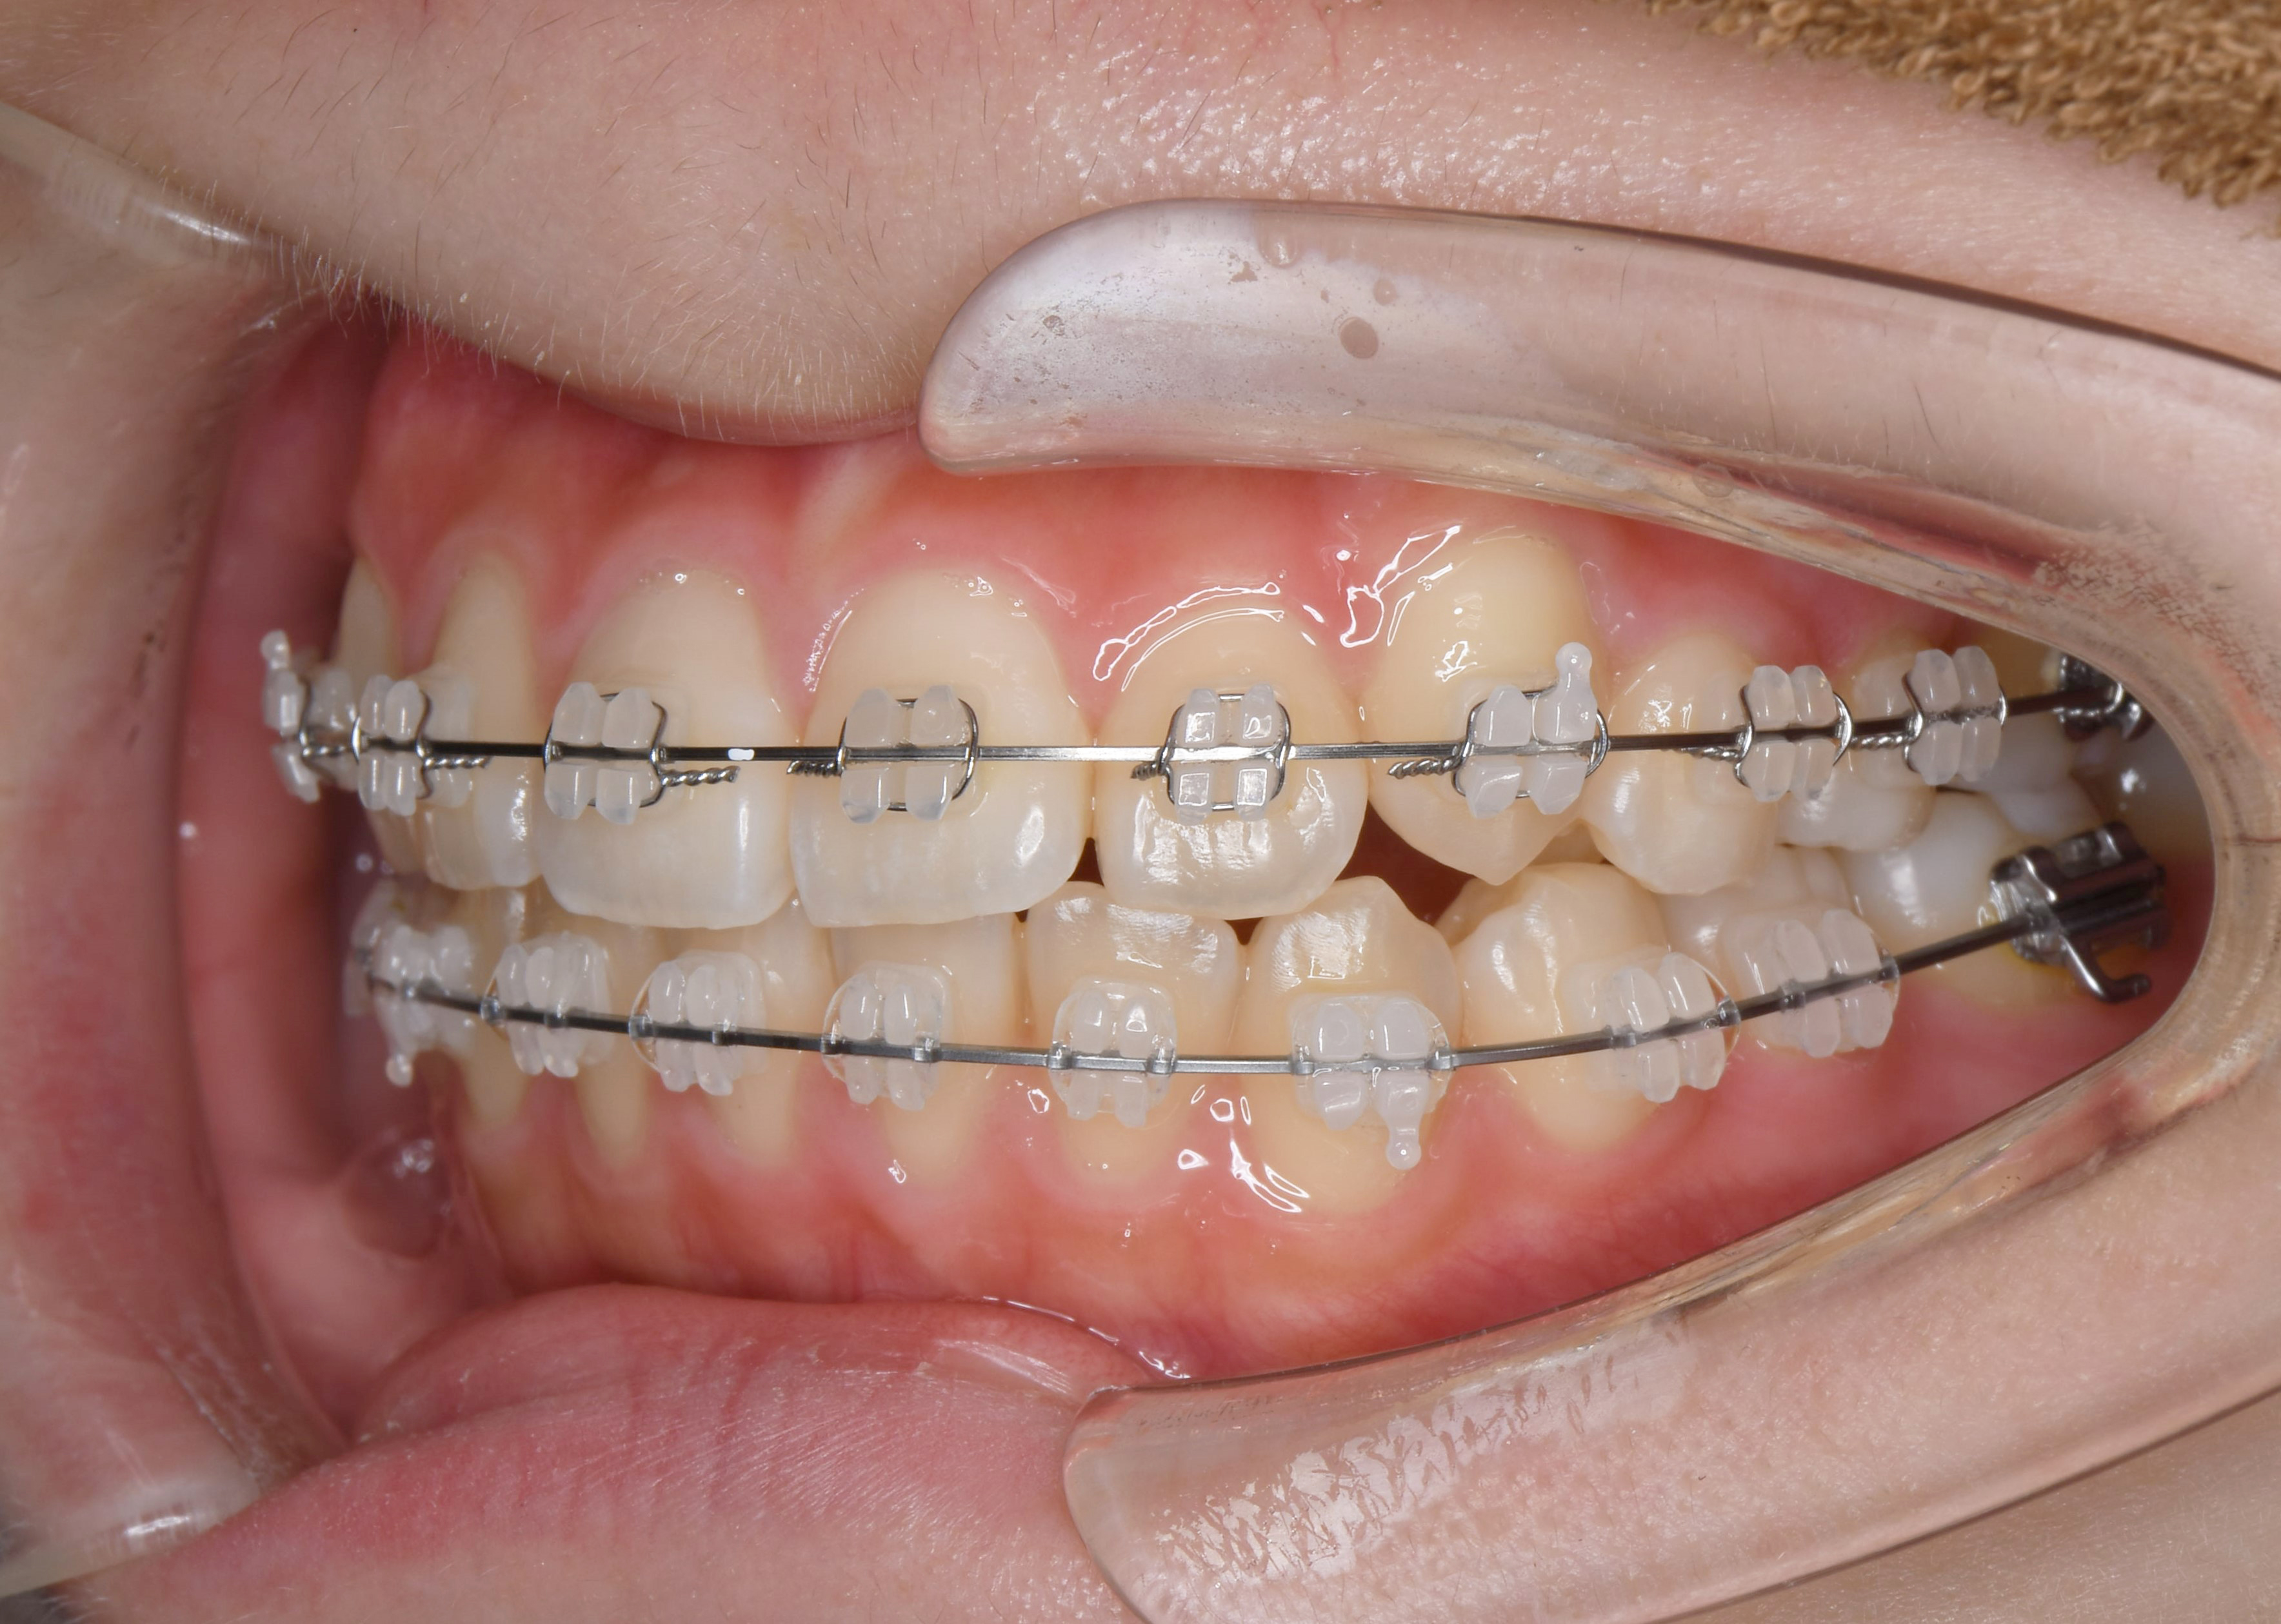

治療前。上顎の前歯の突出の改善を主訴に来院。上顎前歯の前方への突出が著しい。また下顎の前歯が上顎の歯茎を噛んでおり、過蓋咬合(ディープバイト)を呈している。上顎前歯の後方移動と過蓋咬合の改善が必要な症例。臼歯部の上下の咬合関係は完全な2級咬合(下顎遠心咬合)であるため、上顎の左右の第一小臼歯だけを抜歯する計画とした。

矯正治療後。上顎の小臼歯を抜歯したスペースを利用することで、上顎前歯が内側にきれいに並んでいることが分かる。過蓋咬合も改善し、個性正常咬合を確立した。上下の歯の数が異なる変則抜歯のケースでは、抜歯本数を最少に出来るものの、下顎第二大臼歯(一番奥の歯)は噛み合わせにあまり参加できない欠点もある。治療計画は、総合的に最善な結果が得られるよう立案し提案することが重要。